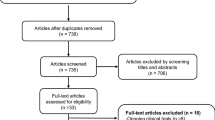

MEDLINE, ISI Web of Science, Cochrane Library, and Scopus databases electronic databases were searched for articles in English published until 29th March 2016. Gray literature (i.e., abstracts or conference proceedings), reviews, case-reports, and non-humans studies were not considered as a priority asset of our systematic review. Studies were identified, combining the following major Medical Subject Headings: “Atypical Parkinsonism” or “Corticobasal Degeneration” or “Multiple System Atrophy” or “Progressive Supranuclear Palsy” and “PET” combined with text and keywords (MEDLINE, for example): ([“Atypical Parkinsonism”, MeSH Terms, OR “Progressive Supranuclear Palsy” OR “Richardson-Steele-Olszewski syndrome” OR “Multiple System Atrophy”, MeSH Terms, OR “Shy-drager syndrome” OR “olivopontocerebellar atrophy” OR “striatonigral degeneration” OR “Corticobasal Ganglionic Degeneration” OR “Corticobasal Degeneration”] AND ]“Positron-Emission Tomography”, MeSH Terms, OR “positron emission tomography” OR “PET”]). Additional eligible studies were identified screening the reference lists of studies included in our analysis.

Inclusion criteria

All selected titles and abstracts were independently reviewed by two authors (FN, MP). Studies were excluded if the title and/or abstract were not appropriate for the aim of the review. Full texts were subsequently obtained for eligible studies or when the relevance of an article could not be certainty excluded. Selected studies were eligible if they met the following criteria: 1) cross-sectional, case control, or longitudinal brain PET studies including PSP, MSA, and CBS patients; 2) published in peer-reviewed journals. Reviews, case-reports and non-human studies were excluded. PET measures included the following radioligands: [11C]raclopride (dopamine D2 receptors), [11C]DTBZ [vesicular monoamine transporter type-2 (VMAT2)]; [18F]FP-CIT [dopamine transporter (DAT)]; H2 15O (brain metabolism); [11C]PK11195 (microglial activation), [18F]FDG (glucose metabolism); [18F]FDDNP (hyperphosphorilated tau); [11C]PiB (amyloid deposition); [11C]flumazenil (GABAA receptors); [11C]diprenorphine (opioid receptors); [11C]PMP [acetylcholinesterase (AChE) activity]; and [11C]NMPB [muscarinic acetylcholine receptors (mAChRs)]. A total of 77 PET studies were identified and reviewed in this article.